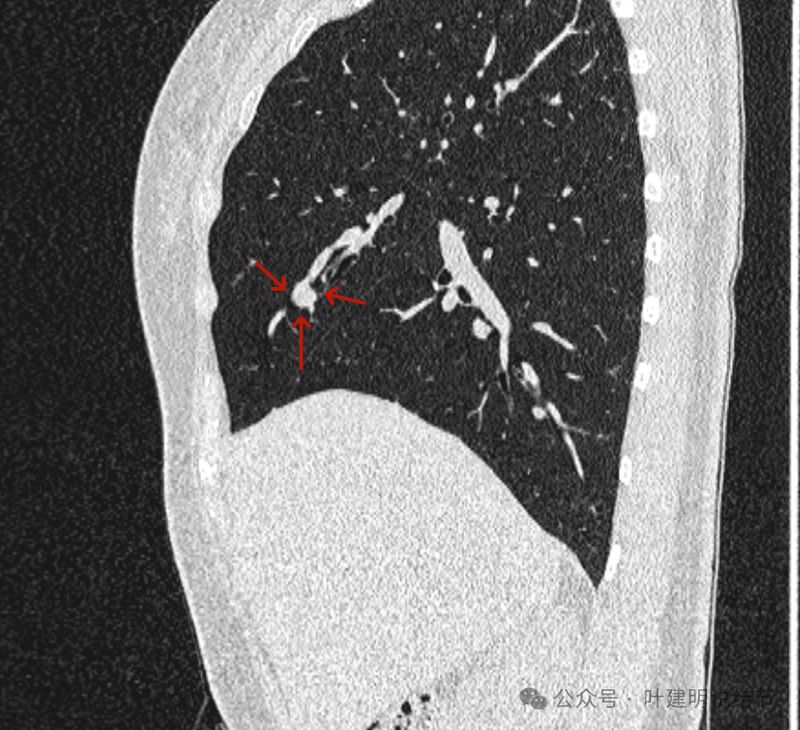

再看矢状位影像:

桔色的是血管,红色的是病灶,两者之间有间隙仍用天蓝色细线标注。

紧挨但仍有缝隙的。

血管贴着病灶,病灶表面略有毛糙之处。

血管有形成轻微血管弯征,两者紧贴。

两支血管夹着病灶,密度不同,有低密度间隙。

病灶与两侧血管关系均密切,明显觉得密度是不一样的,血管的密度略高,结节的略低。

病赤与血管在蓝色箭头处失去间隙,像是侵蚀血管壁,造成血管受侵犯破坏。病灶是软组织密度的,而且整体看有膨胀感。

病灶密度稍不均。表面不光滑。

病灶与边上血管间隙不清。

桔色箭头所示的血管受压稍有移位。

密度不同,关系密切。

边缘区域也是有膨胀感。

血管与病灶脱开后的样子。

边缘区也是基本上实性的。